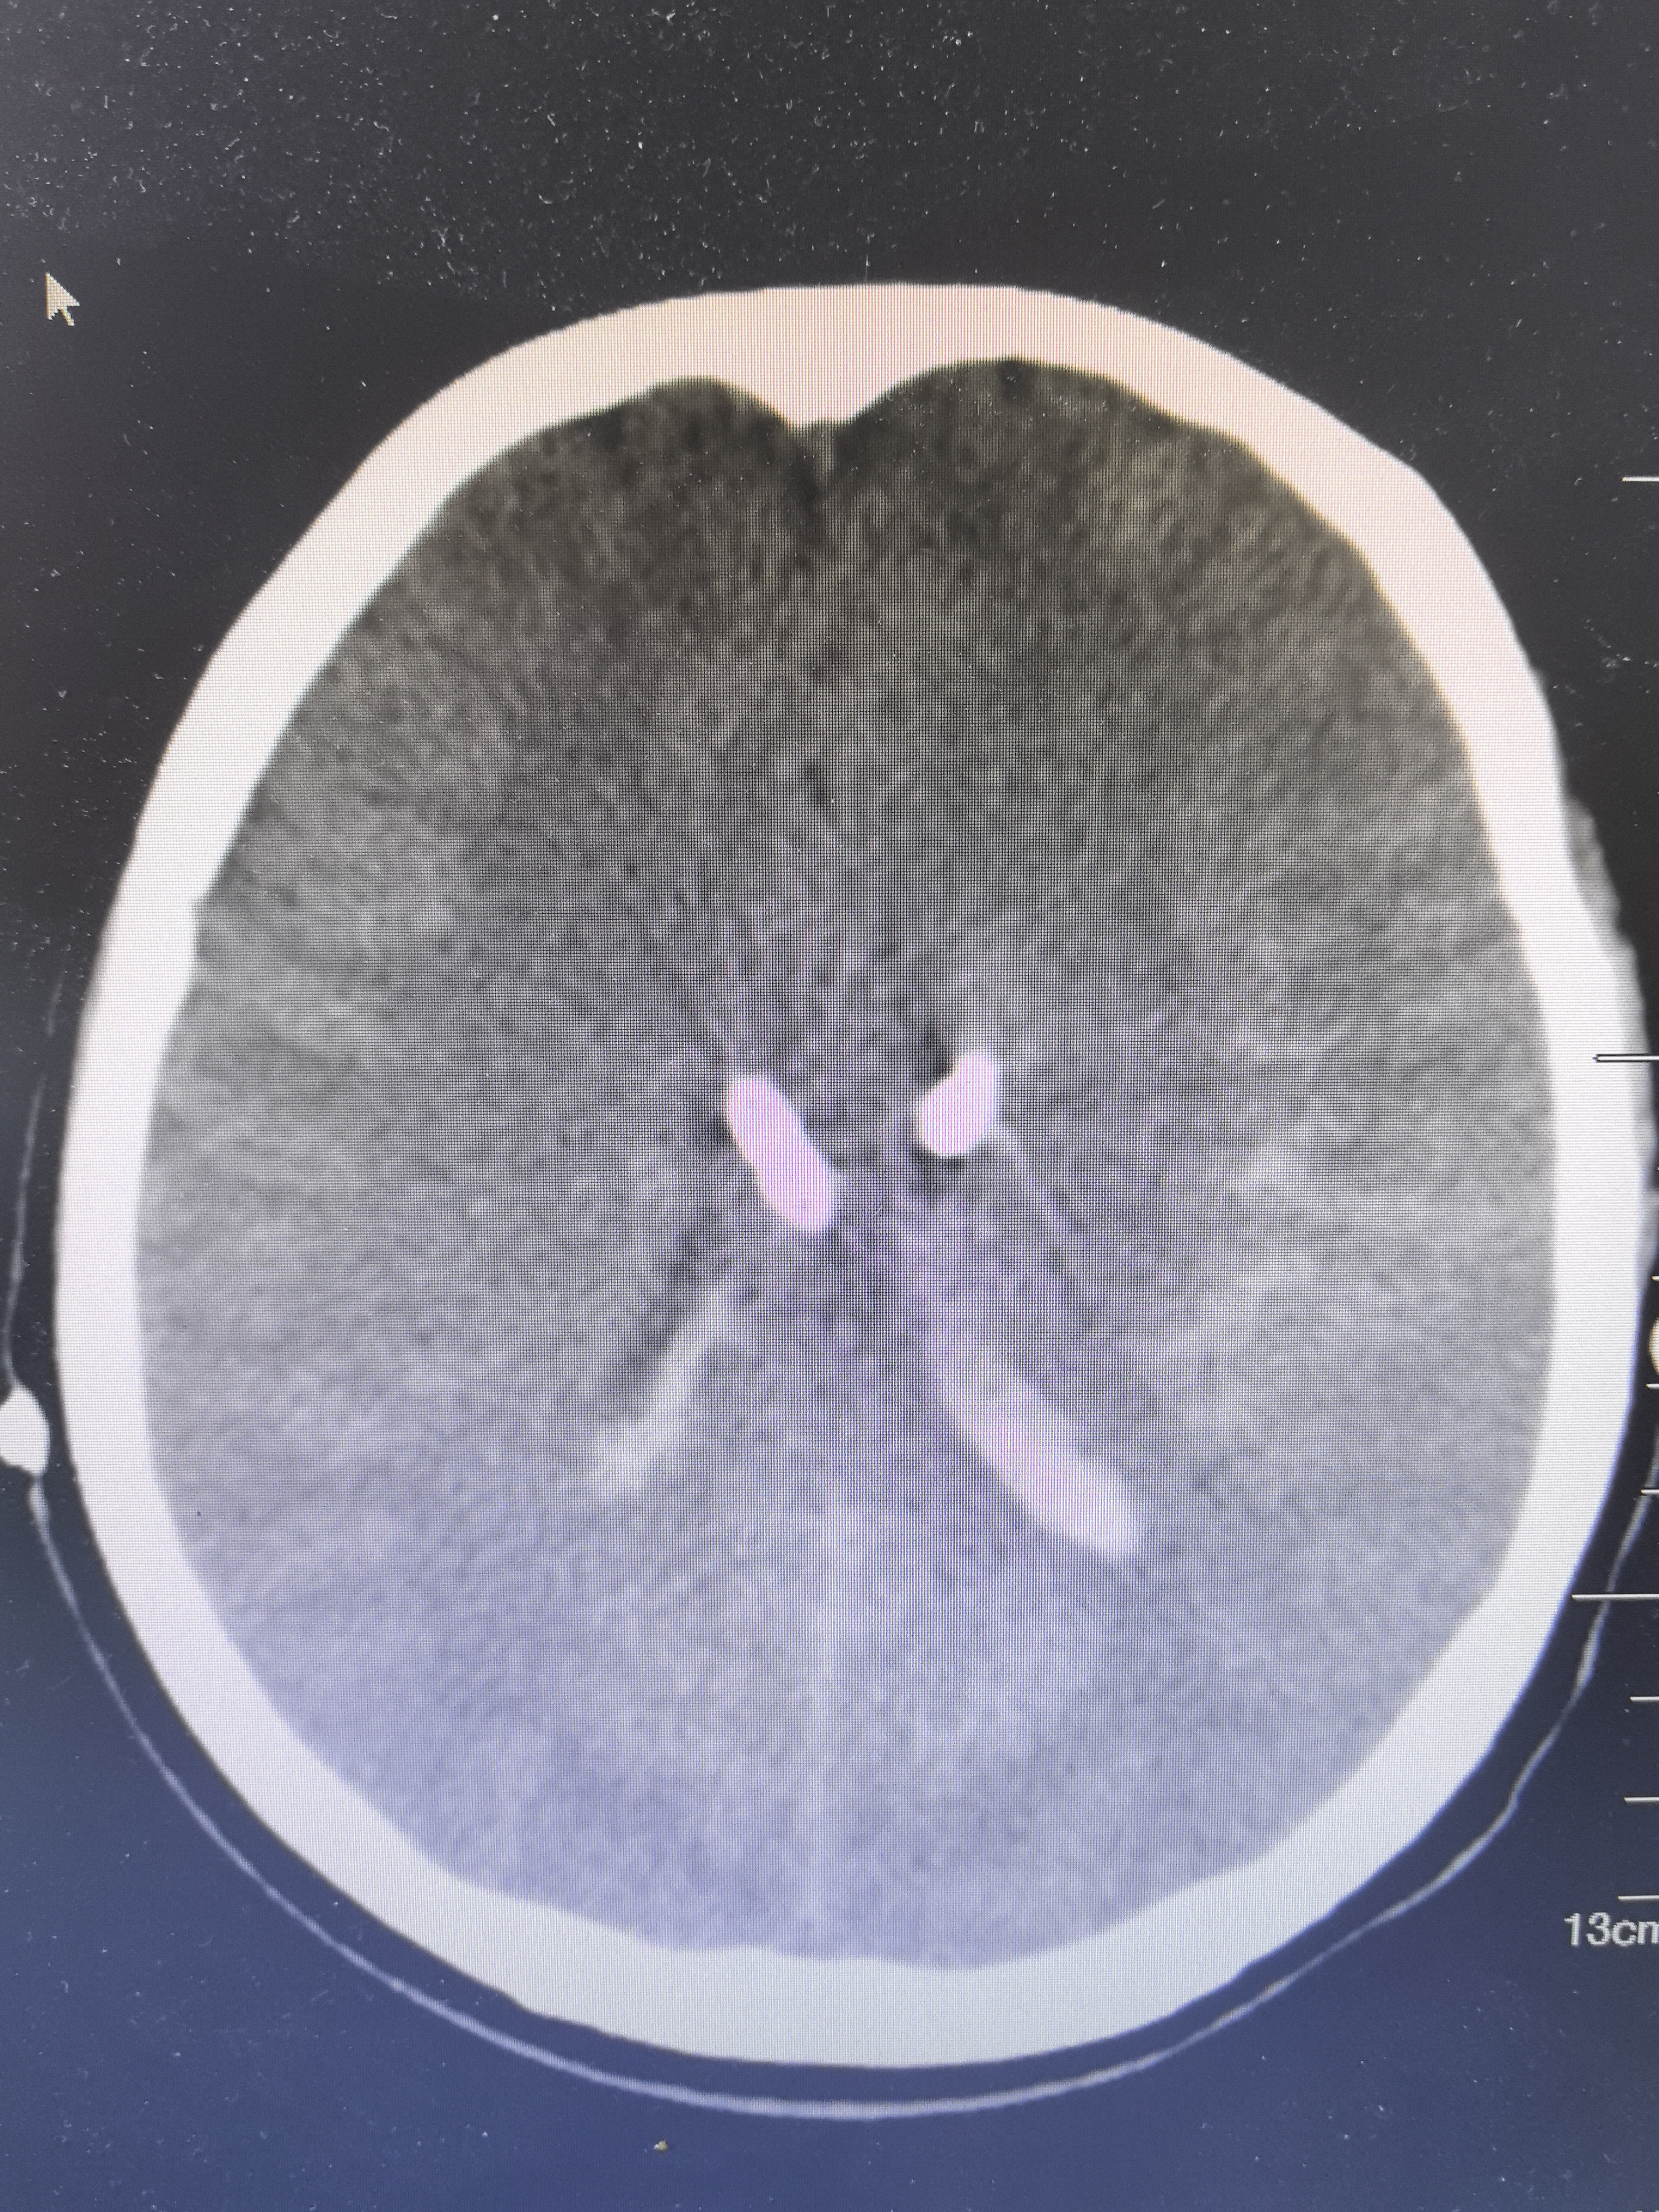

头CT显示蛛网膜下腔出血破入脑室及脑内,三四脑室铸型

CTA阴性